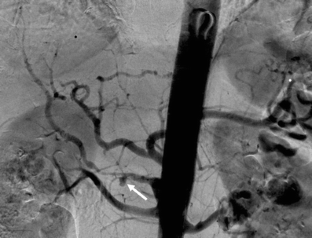

Fig. 3